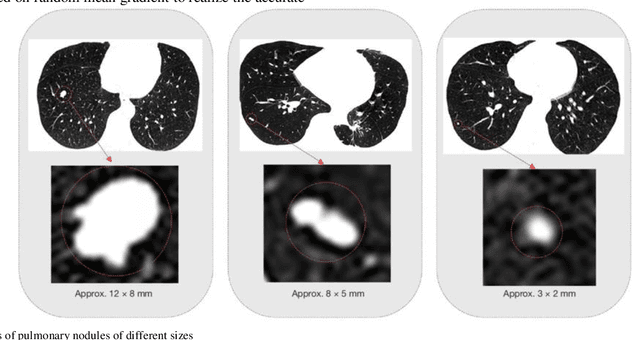

Abstract:The 3D simulation model of the lung was established by using the reconstruction method. A computer aided pulmonary nodule detection model was constructed. The process iterates over the images to refine the lung nodule recognition model based on neural networks. It is integrated with 3D virtual modeling technology to improve the interactivity of the system, so as to achieve intelligent recognition of lung nodules. A 3D RCNN (Region-based Convolutional Neural Network) was utilized for feature extraction and nodule identification. The LUNA16 large sample database was used as the research dataset. FROC (Free-response Receiver Operating Characteristic) analysis was applied to evaluate the model, calculating sensitivity at various false positive rates to derive the average FROC. Compared with conventional diagnostic methods, the recognition rate was significantly improved. This technique facilitates the detection of pulmonary abnormalities at an initial phase, which holds immense value for the prompt diagnosis of lung malignancies.